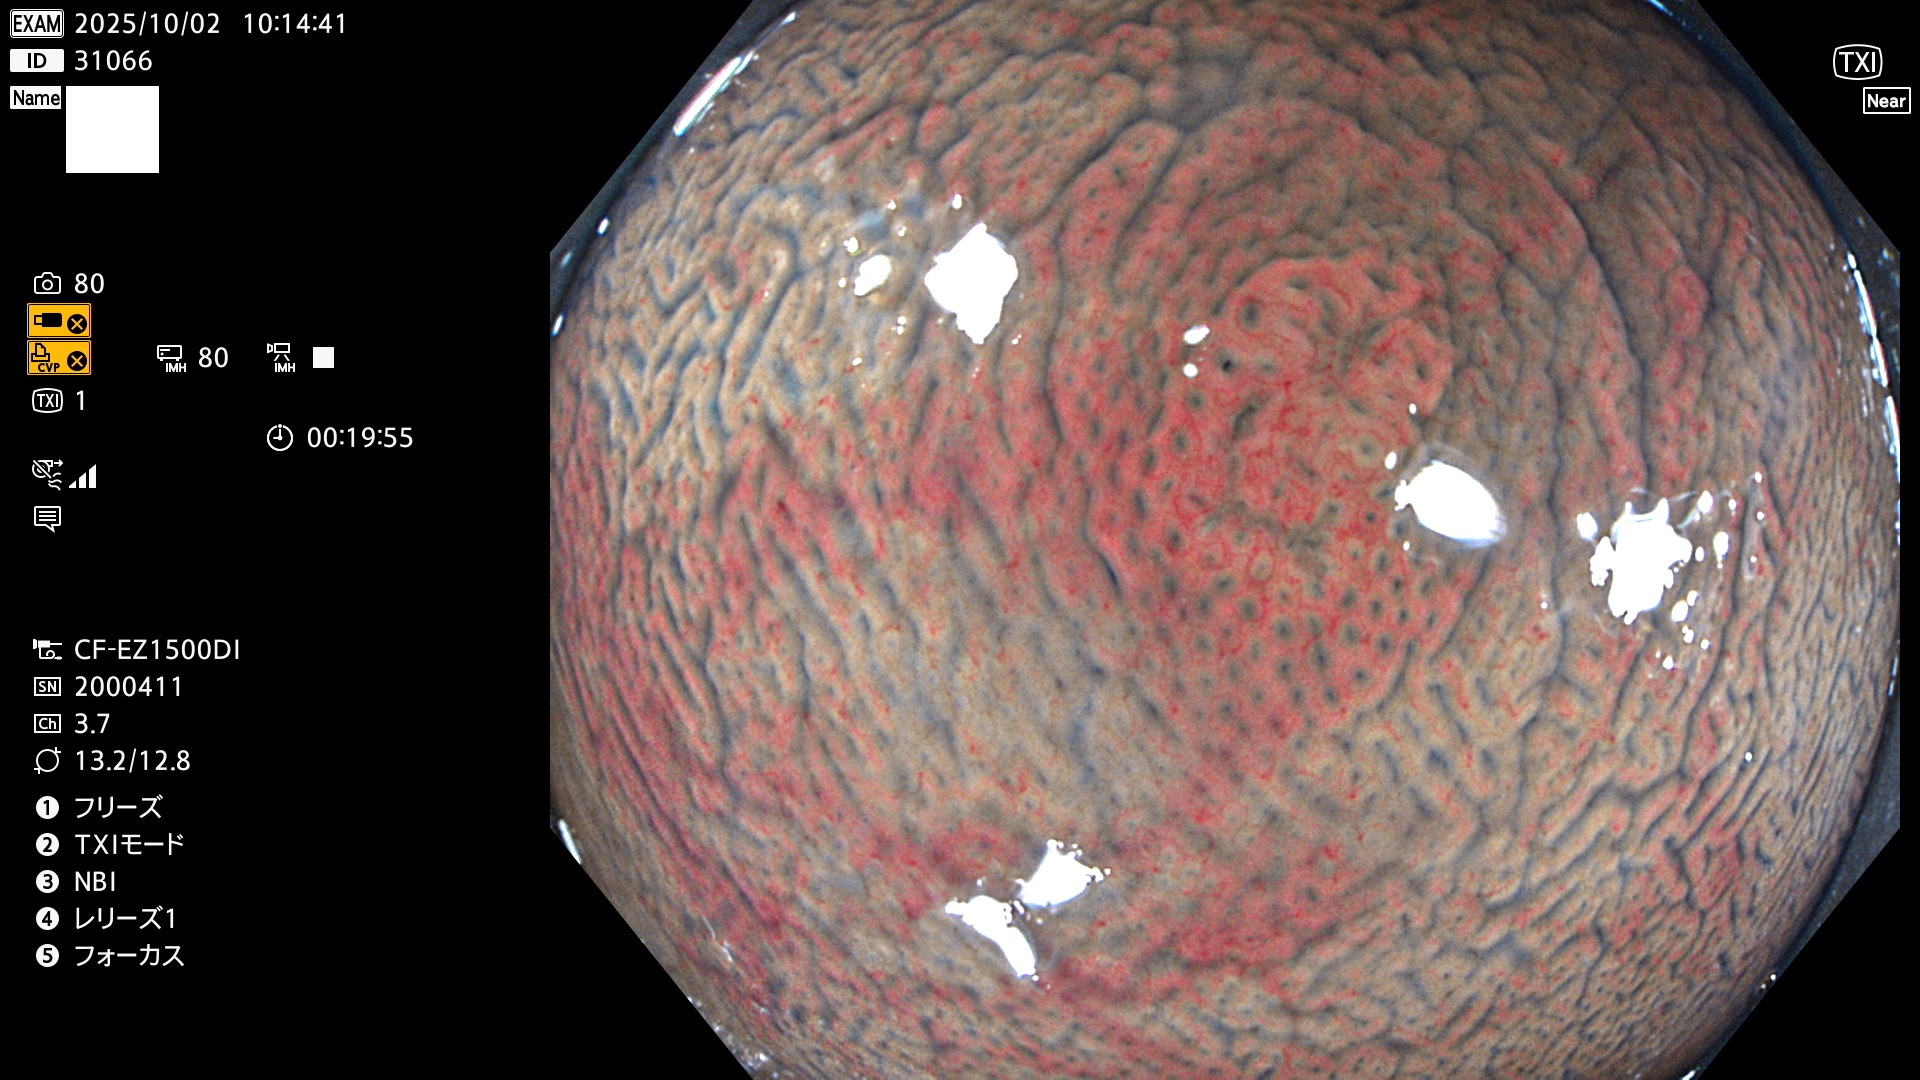

完全に平坦な物をUb、陥凹している物をUcと呼びます。Ubは認識が困難で、Ucはびらん(炎症)と紛らわしいために見落とされやすく、「内視鏡後・大腸癌」の原因になります。

専門的)Uc=De Novo癌? 内視鏡の解像度が低かった時代、このような説もありました。しかし今日の高精度内視鏡では良性の微小なUc型腺腫(APC遺伝子異常の腺腫)が日常的に見つかります。Ucこそが多段階発癌(Adenoma-Carcinoma Sequence)のMain Routeです。

毎週の検査(木・金・土・日)に発見されたUbとUc型・腺腫を、その週の日曜の夜にUPし1週間、提示します。

写真公開の目的は「透明性・信憑性の担保」ですが、公開を希望されない方はメールで御連絡下さい。直ちに削除いたします。

2025年10月2日〜10月5日の4日間(40件)で9個 (Uc_ADR=9個/40人=23%)